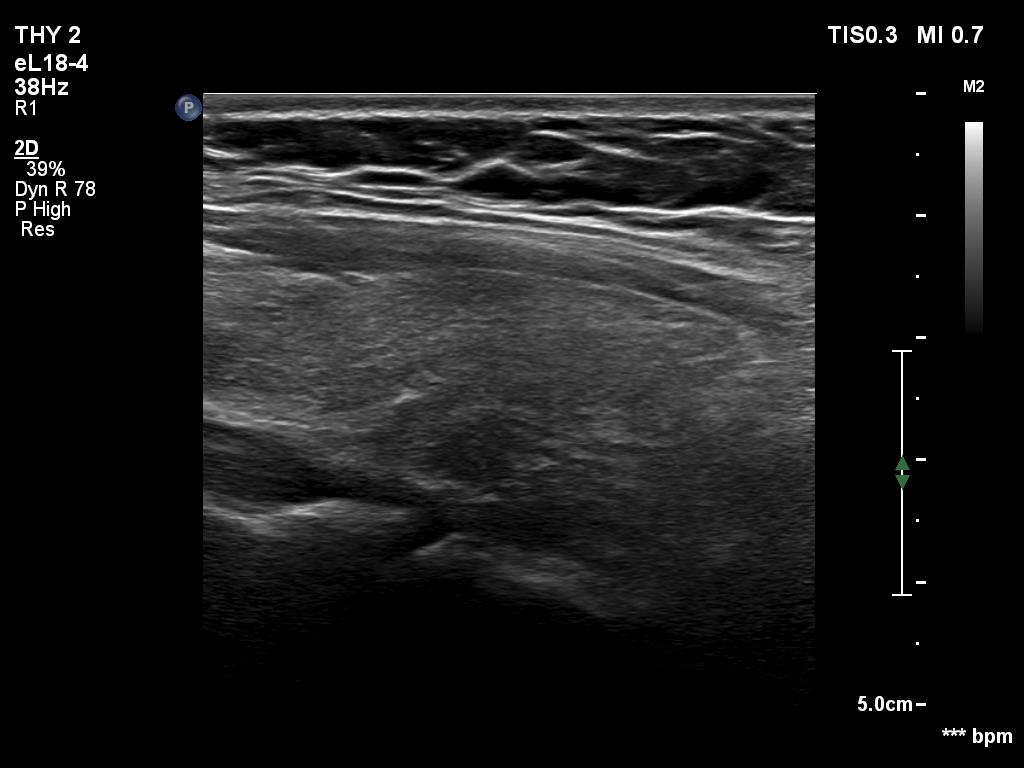

Ultrasonography. The thyroid was echonormal. Using higher frequency three discrete hypoechoic lesions were found, one in the middle dorsal part of the right lobe, one in the middle and a third one in the lower dorsal part of the left lobe. By decreasing the frequency, the presence of only the third one could be confirmed.

Comment. It is a rule that larger the distance from the probe worse the permeability of ultrasound wave. This can lead in certain patients (overweighted ones or frequently in men) that the dorsal part of the thyroid lobe can deceptively look darker, i.e. hypoechoic. If we have any doubt, by lowering the frequency i.e. increasing the penetrance, the real situation can be much better to judge.

This happened in this patient. If we would trust the pattern gained by higher frequency settings, we would falsely diagnose at least one additional nodule.